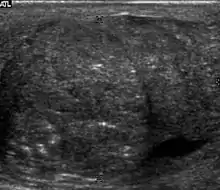

![]() Sonography of a normal testis. The normal testis presents as a structure having homogeneous, medium level, granular echotexture. The mediastinum testis appears as the

hyperechoic region located at the periphery of the testis as seen in this figure. | |

The normal adult testis is an ovoid structure measuring 3 cm in anterior-posterior dimension, 2–4 cm in width, and 3–5 cm in length. The weight of each testis normally ranges from 12.5 to 19 g. Both the sizes and weights of the testes normally decrease with age. At ultrasound, the normal testis has a homogeneous, medium-level, granular echotexture. The testicle is surrounded by a dense white fibrous capsule, the tunica albuginea, which is often not visualized in the absence of intrascrotal fluid. However, the tunica is often seen as an echogenic structure where it invaginates into the testis to form the mediastinum testis. In the testis, the seminiferous tubules converge to form the rete testes, which is located in the mediastinum testis. The rete testis connects to the epididymal head via the efferent ductules. The epididymis is located posterolateral to the testis and measures 6–7 cm in length. At sonography, the epididymis is normally iso- or slightly hyperechoic to the normal testis and its echo texture may be coarser. The head is the largest and most easily identified portion of the epididymis. It is located superolateral to the upper pole of the testicle and is often seen on paramedian views of the testis. The normal epididymal body and tail are smaller and more variable in position.